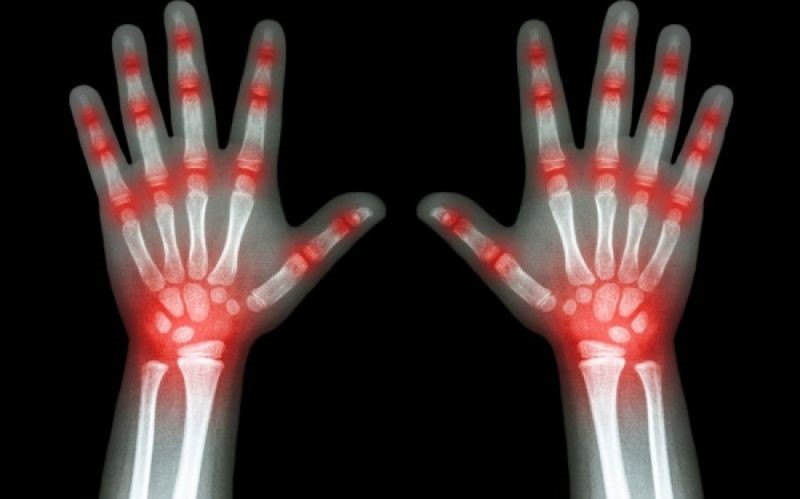

Τα 12 πρώιμα συμπτώματα ρευματοειδούς αρθρίτιδας

Ρευματοειδής αρθρίτιδα (ΡΑ) – Σε άτομα με ΡΑ, το ανοσοποιητικό σύστημα προσβάλλει εσφαλμένα τα κύτταρα στην εσωτερική επένδυση των αρθρώσεων, με αποτέλεσμα την φλεγμονή τους. Αυτό κάνει τις αρθρώσεις να πρηστούν, να σκληρύνουν και να σας πονούν.

Η ρευματοειδής αρθρίτιδα παρουσιάζει πόνο των αρθρώσεων στα δάκτυλα, τους καρπούς και τα πόδια. Η φλεγμονή καθιστά την εσωτερική επένδυση της άρθρωσης παχύτερη και επίσης προκαλεί την παραγωγή επιπλέον αρθριτικού υγρού.

Και οι δύο αυτοί παράγοντες ασκούν πίεση στην κάψουλα που περιβάλλει την άρθρωση και ερεθίζουν τις νευρικές απολήξεις που περιέχει, προκαλώντας πόνο.

7. Οίδημα (πρήξιμο) των αρθρώσεων

Οι αρθρώσεις που φαίνονται πρησμένες στα χέρια και τα πόδια είναι ένα τυπικό σημάδι της ΡΑ. Το πρήξιμο των αρθρώσεων τείνει να είναι πιο εμφανές καθώς η ρευματοειδής αρθρίτιδα εξελίσσεται, αλλά το ελαφρύ πρήξιμο μπορεί να είναι ένα πρώιμο σημάδι.

8. Ερυθρότητα των αρθρώσεων

Η φλεγμονή στις αρθρώσεις μπορεί να τους προσδώσει μια κοκκινωπή απόχρωση. Ο αποχρωματισμός του δέρματος γύρω από τις αρθρώσεις στα χέρια και τα πόδια είναι ένα σημάδι της ΡΑ.

Η ερυθρότητα συμβαίνει επειδή η φλεγμονή προκαλεί διεύρυνση των αιμοφόρων αγγείων στο περιβάλλον δέρμα. Τα ευρύτερα αγγεία επιτρέπουν την ροή περισσότερου αίματος σε αυτήν την περιοχή, δίνοντας στο δέρμα κοκκινωπή εμφάνιση.